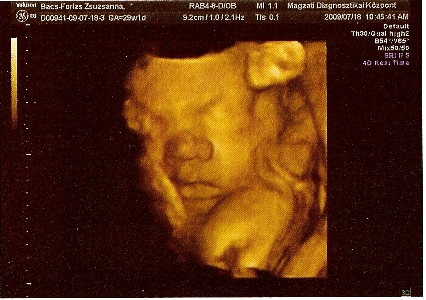

Megkérdezte, hogy hányat tettünk vissza? Én mondtam, hogy múlt héten egy volt. A férjem fogta fel a kérdést és válaszolta, hogy 3-at. Én annyira féltem, hogy nem él, hogy nem is tudtam koncentrálni. Erre Ö azt mondta, hogy itt vannak. Fel sem fogtam, nem akartam elhinni. A férjemet figyeltem, aki egyre sápadtabb volt. Kérdeztem, hogy mind a három? Élnek? A 17x17mm-es petezsákomban 5,2mm CTL méretű baba van szuper erős szívhanggal, annyira jó volt hallgatni, azóta is csak arra tudok gondolni. A 15x15mm-es petezsákban még csak lüktetős szívecske van, de ott is szép szikhólyag mint az előzőnél, és van még egy 9x9mm-es petezsákom, amiben baba még nem látszik, de azt mondta V.-doki, hogy ő sokáig vándorolt és csak nemrég ágyazódott be, jövő keddre kiderül, hogy mi van vele.

Próbálok feltenni képet, bár csak a mobilommal tudom itt a balcsin lefotózni az uhus képet, így nem lesz jó minőség.